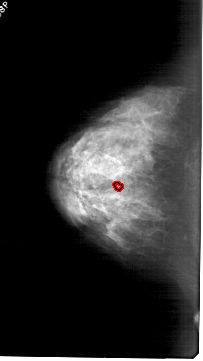

A_1803_1.LEFT_CC

LEFT_CC LINES 6121 PIXELS_PER_LINE 3451 BITS_PER_PIXEL 12 RESOLUTION 43.5 OVERLAY

FILE: A_1803_1.LEFT_CC.OVERLAY

TOTAL_ABNORMALITIES 1

ABNORMALITY 1

LESION_TYPE CALCIFICATION TYPE PLEOMORPHIC DISTRIBUTION CLUSTERED

ASSESSMENT 4

SUBTLETY 2

PATHOLOGY BENIGN

TOTAL_OUTLINES 1